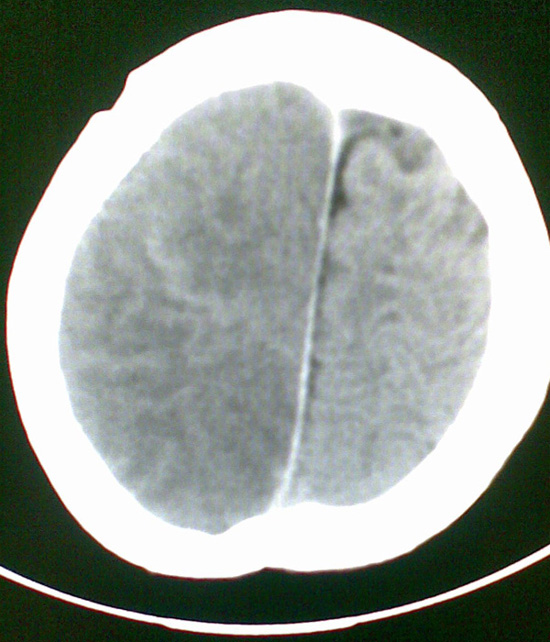

男4岁,反复抽搐多年,今早再次大抽搐,伴昏迷

考虑---右侧大脑半球脑梗死

右侧大脑半球密度减低,脑组织肿胀,占位?建议增强。

考虑脑梗塞. kaolv 血管病变---烟雾病可能

1)右侧大脑半球大面积脑梗塞。2)双侧额叶脑软化灶。3)脑萎缩。

建议:必要时行dsa检查排除烟雾病可能。

右侧半球梗塞,多发软化灶,考虑血管畸形继发,进一步检查。

右侧大脑半球大面积脑梗塞。双侧额叶脑软化灶。考虑血管畸形继发,建议进一步检查。

1右侧大面积脑梗死2左侧额颞部软化灶。